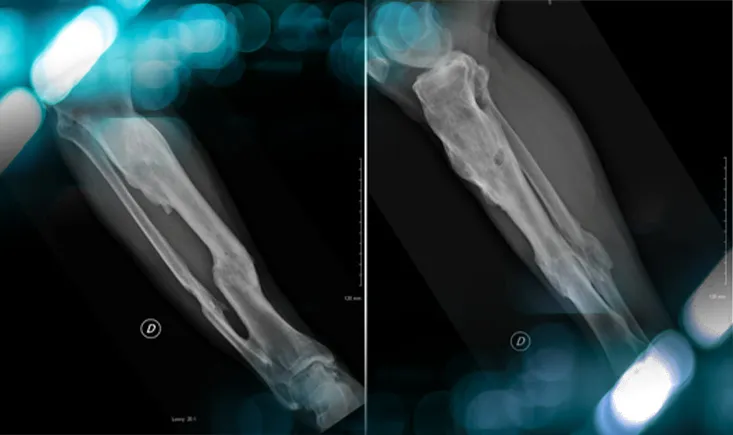

Management of an osteolytic lesion of the distal femur affecting the knee joint

Explore the case of a patient with knee pain, revealing more than just an injury, and uncover the management strategies for osteolytic lesions…